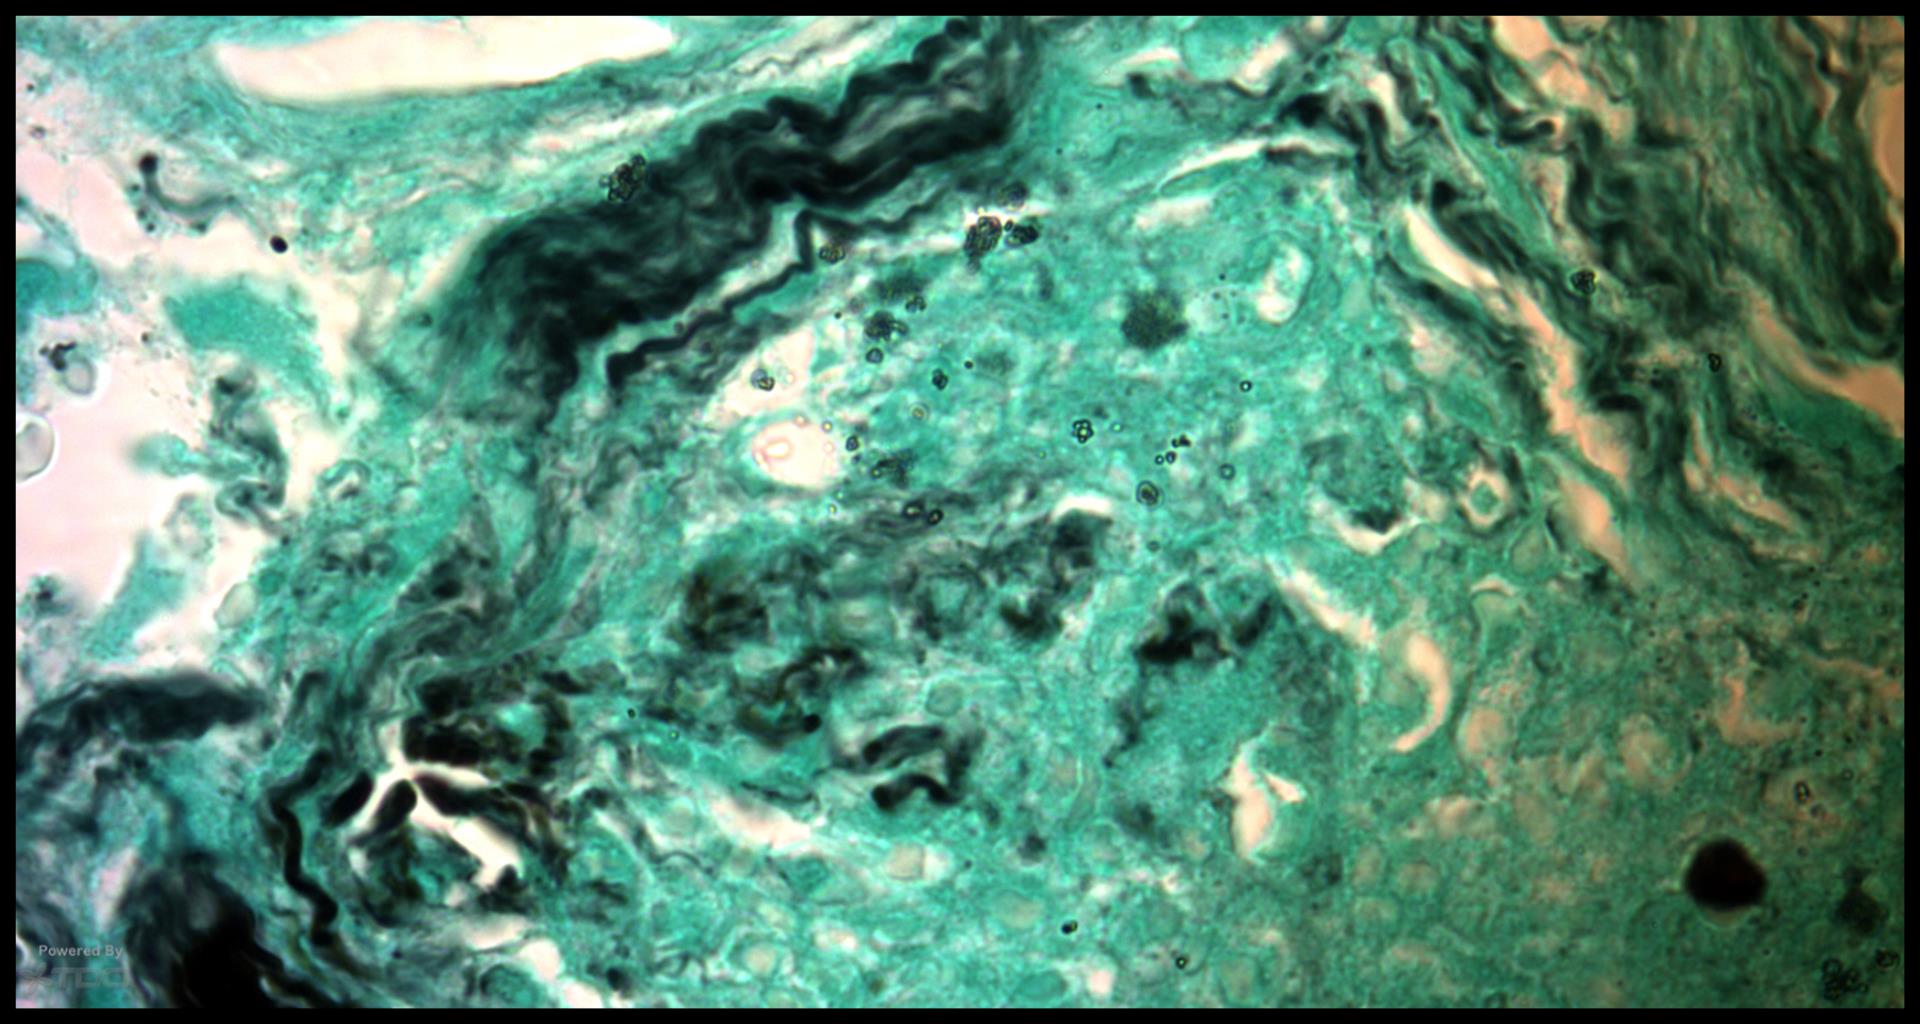

Older TDO’ers may remember this case that Rick sent me in 2012 from a surgery he did.. There was some bacterial morphotypes seen along the canal wall, but not very much. But on the outer root surface there was a lot of inflammation and a fungal stain suggests why…. gbc